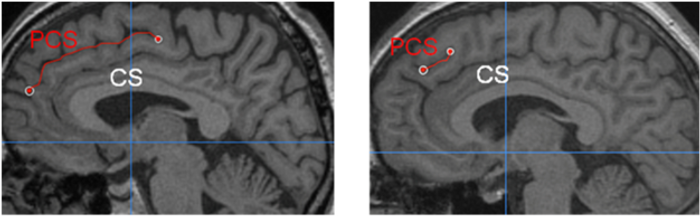

Paracingulate Sulcus Pcs Measurement For 2 Example Images Note The Download Scientific Diagram